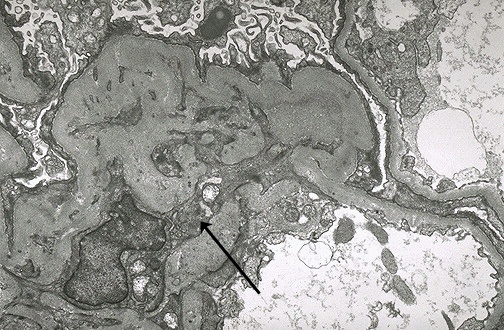

| This electron micrograph demonstrates a mesangial cell at the lower left that is interposing its cytoplasm at the arrow into the basement membrane, leading to splitting and reduplication of basement membrane that is piled up above the mesangial cytoplasm in this micrograph. This is MPGN type I. These characteristic EM changes occur when the mesangial cell (which has a macrophage-like function) goes after subendothelial immune deposits, but makes a mess of the basement membrane in the process. |